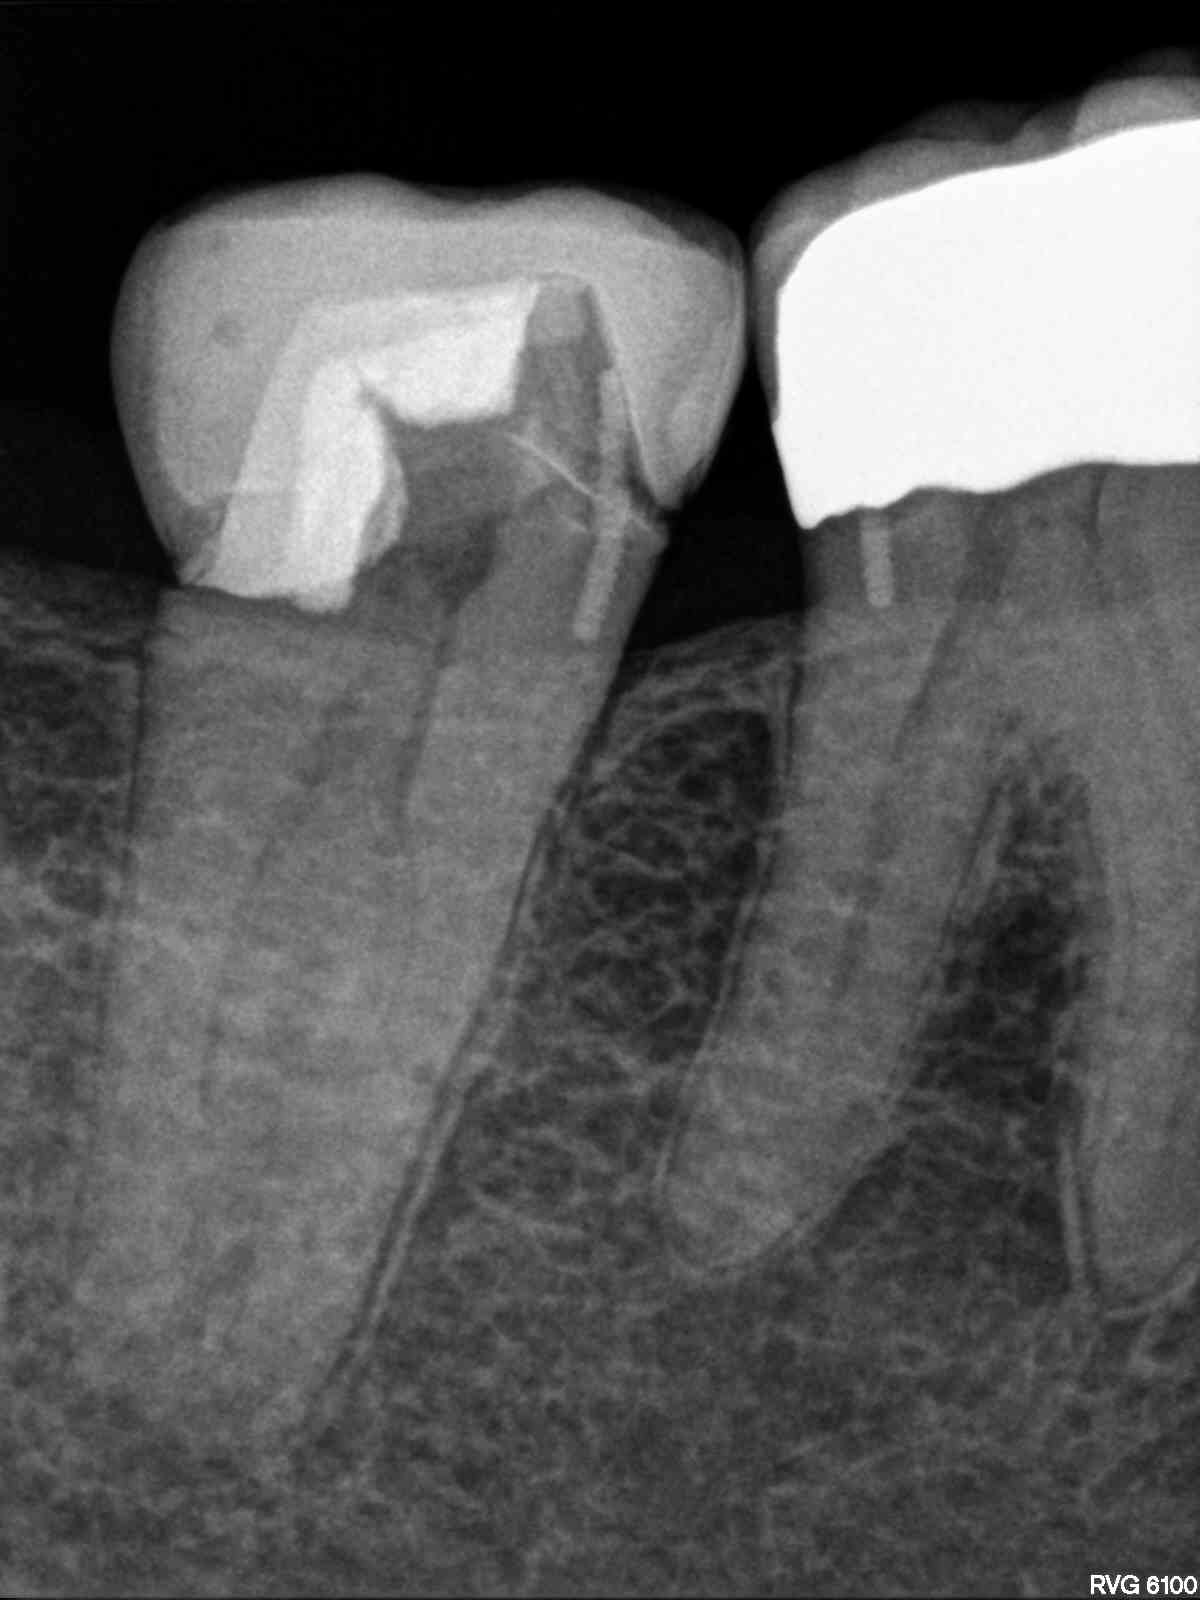

„C“ ja – „C“ nein